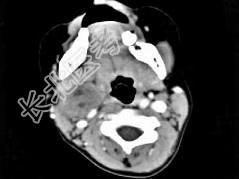

- 单项选择题女,4岁, 右侧颈部可扪及一包块约两个月,无热无痛, CT如图所示,最可能的诊断为  (    )